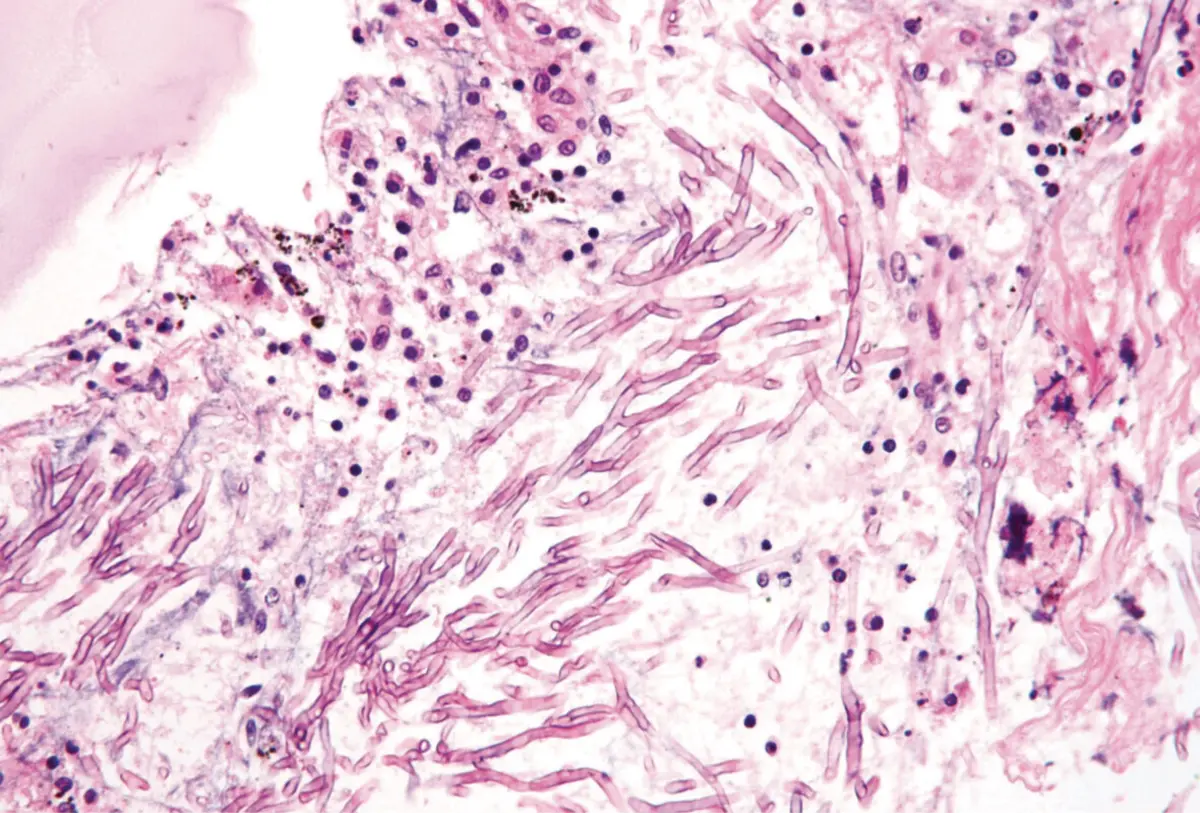

Os exames revelaram uma inflamação na parte inferior do pulmão direito, e uma broncoscopia confirmou o diagnóstico de aspergilose, uma infeção fúngica causada pelo fungo Aspergillus.

A análise confirmou a presença do mesmo fungo nos tecidos das peças de roupa. As meias suadas criam um ambiente propício para a proliferação do Aspergillus, e a inalação pode causar infeções respiratórias, especialmente em pessoas com sistema imunológico comprometido.